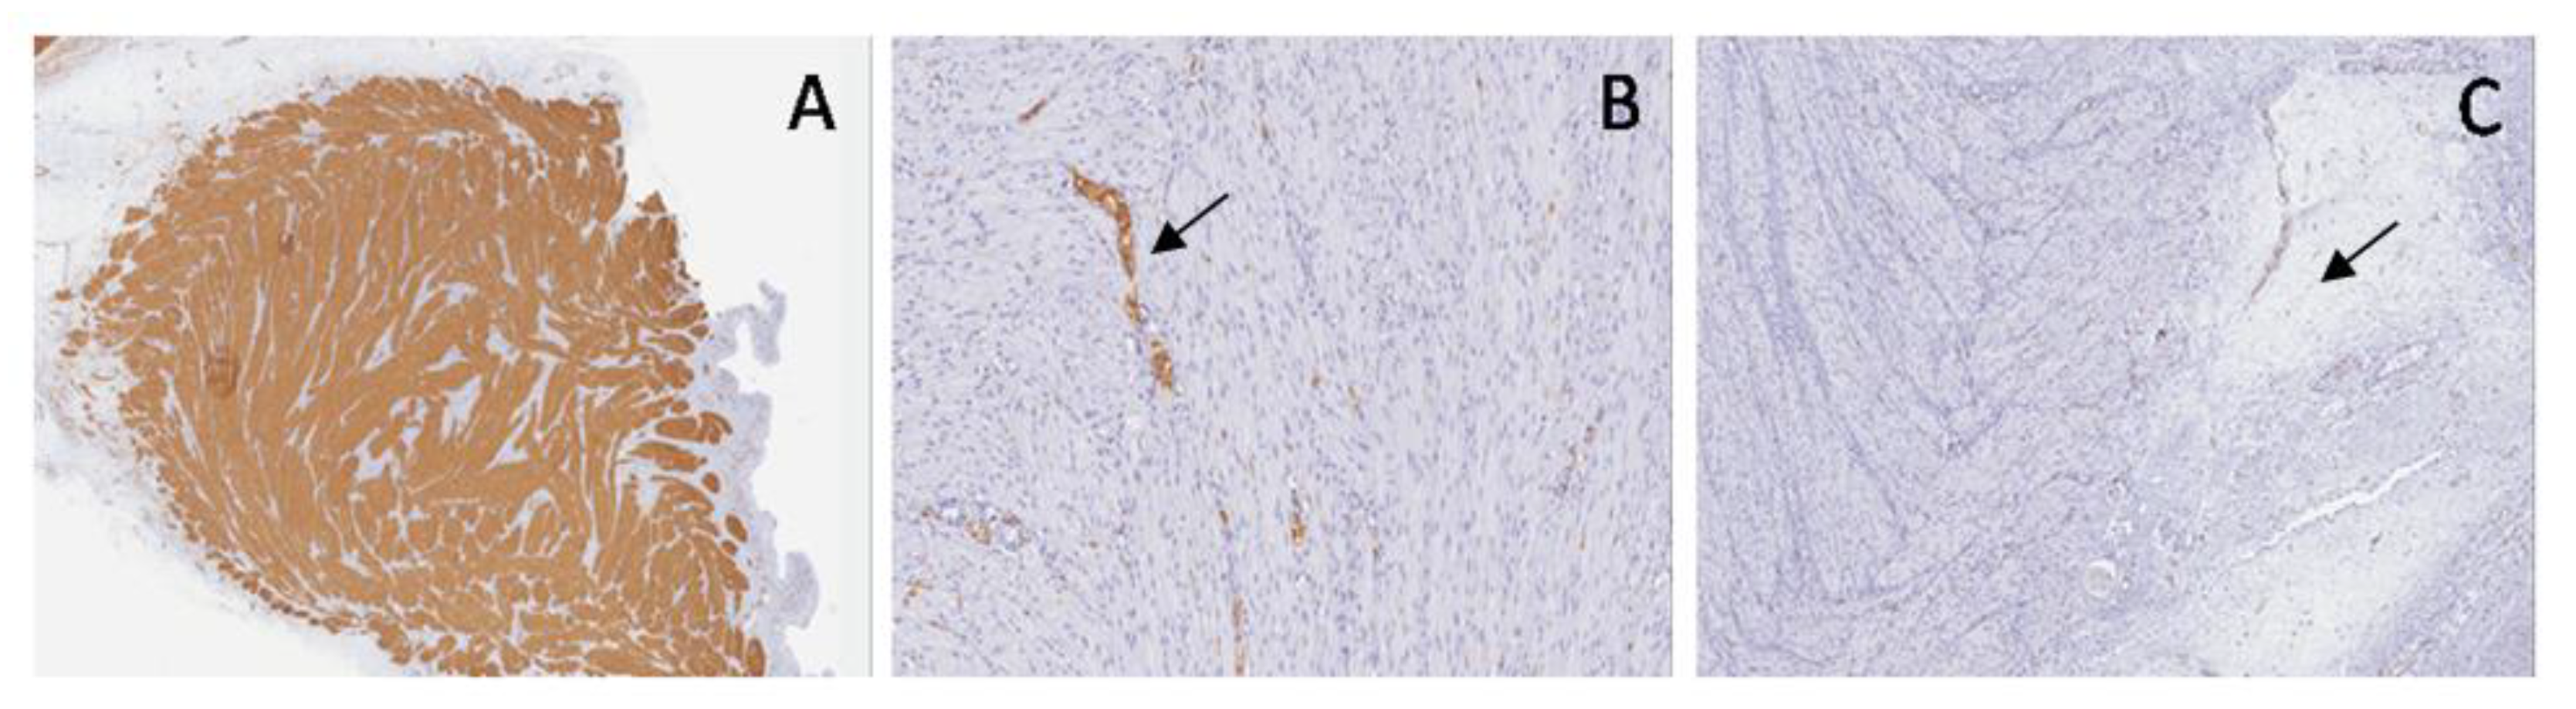

Large and small bowel: SMA stained longitudinal and transverse muscular layers and interposed embryonal mesenchyme; S100 protein marked submucosal and myenteric plexuses with neural and ganglion cells; WT1c was shown in ganglion cells and their cytoplasmic extensions (Figure 4).

Figure 4. Normal bowel. Immunohistochemical staining shows: SMA (A) in longitudinal and transverse muscular layers (arrow), S100 (B) in submucosal and myenteric plexuses (arrow) and WT1c (C) in ganglion cells (arrow).